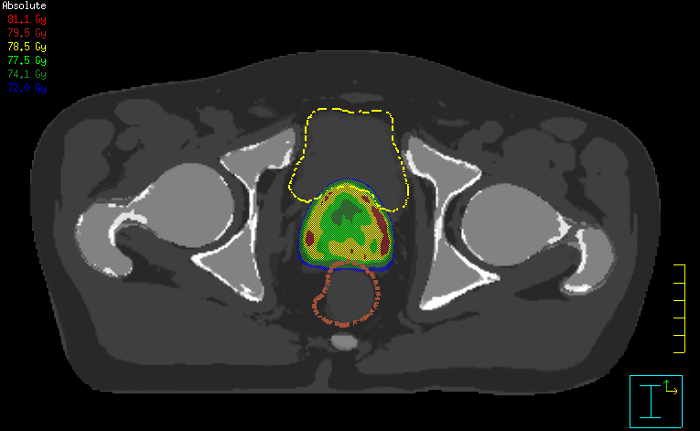

Our innovative MRCAT (MR for Calculating ATtenuation) clinical applications lets you plan radiation therapy using MRI as primary imaging modality. Within just one, fast MR exam, MRCAT provides both excellent soft-tissue contrast for target and OAR delineation and CT-like density information for dose calculations.

This not only extends the benefits of MRI’s excellent soft-tissue contrast to radiotherapy planning, but it also eliminates arduous, error-prone CT-MRI registration from the process, reducing uncertainties and complexity.